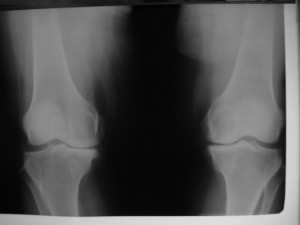

Total Diz Protezi

Total Diz Protezi ameliyatı 50 yılı aşkın bir süredir tüm dünya üzerinde bir çok farklı merkezde başarı ile uygulanmaktadır. Daha önceki yıllarda bu protezlerin ömürleri 10-15 yıl olarak bilinmekteyken, artık gelişen implant teknolojisi, artan bilgi paylaşımı ve ameliyat teknikleri ile bu yıl çok daha üst seviyelere çekilmiştir.

Total diz protezi (TDP) primer olarak dizde ciddi ağrıya neden olan artritli ( halk arasında diz kireçlemesi olarak bilinir) hastalarda endikedir. Özellikle ağrı ve dizde fonksiyon bozukluğu hastaların yaşam kalitesinde ciddi bozulmalara sebep olmaktadır. Hastaların bu ameliyatı olmadan önce konservatif tedavilerin tümünden fayda görmemiş olması gerekmektedir.

Total Diz Protez ameliyatı kliniğimizde endikasyon dahiline her yaşa başarı ile uygulanmaktadır. Örnek olgumuz: